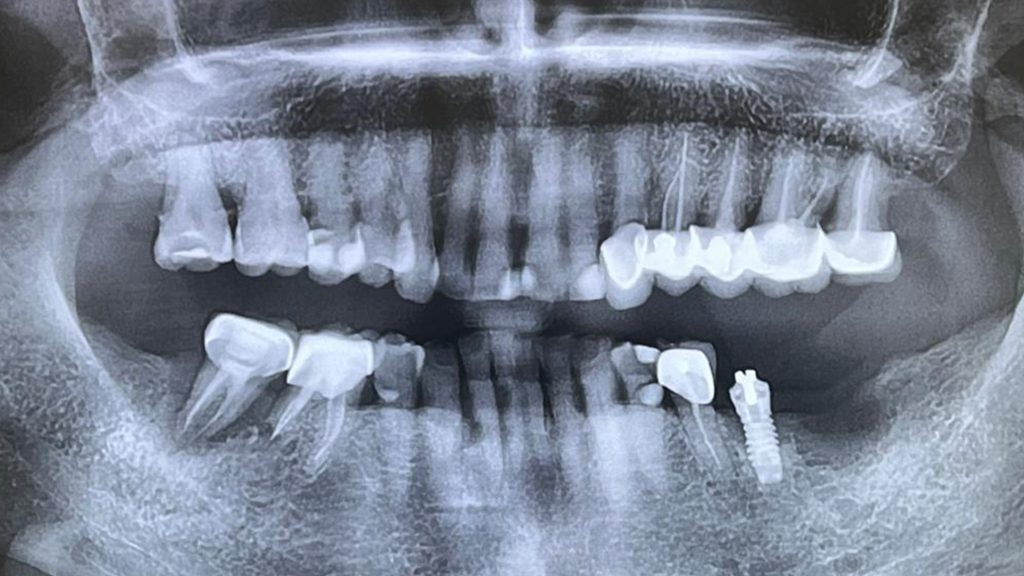

une chirurgie en direct commentée par le Dr Gérard Scortecci, réalisée dans le secteur 3 mandibulaire gauche, en 37.

La patiente présentait une perte significative du support osseux, datant de plus de 15 ans, et ayant conduit à une cavitation importante de la zone concernée.

L’utilisation de l’insertion matérale s’est révélée particulièrement pertinente pour cette opération.